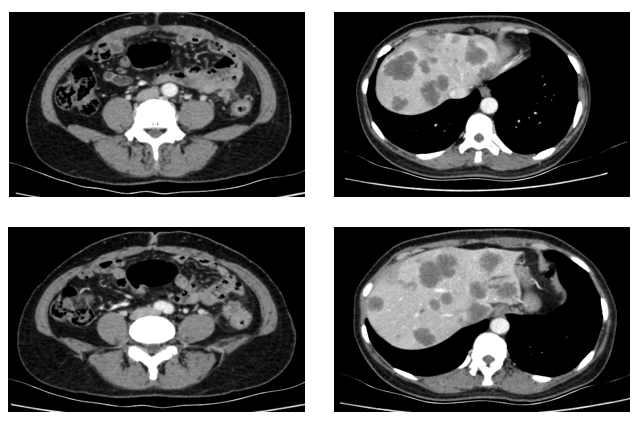

于2021.04.17行“FOLFOX6”方案化疗1周期,行“奥沙利铂”化疗时,出现严重过敏。因患者基因状态为RAS,BRAF野生型,第2周期始给予“FOLFIRI+西妥昔单抗”,在治疗过程中,肿瘤标志物持续下降,影像学也显示肝脏病灶明显缩小。疗效评价PR,在2021-09-25在局麻DSA下行“肝动脉造影并化疗灌注栓塞术”。

肿瘤初次进展(2021-11-30)

患者于2021年11月30号复查时,肺上病灶增大增多,肝脏病灶稍增大,肿瘤标志物增高,整体疗效评价PD,考虑一线治疗进展。